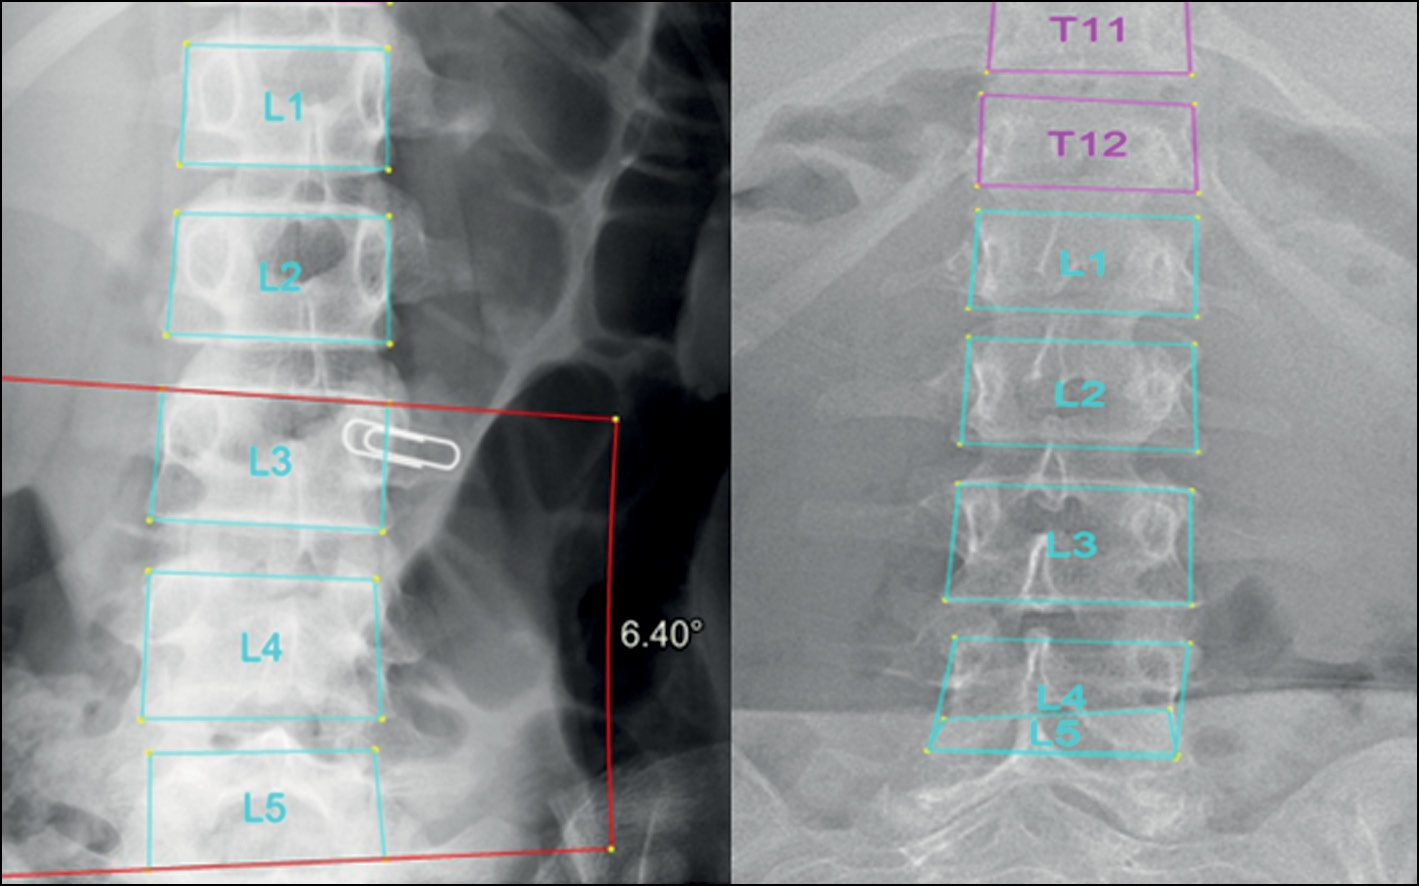

In addition, when using the program, the radiologist can change vertebral markings made by the system automatically. This is very essential to overcome any errors in vertebral markings that can cause a false final result. Further analysis of the results showed that the inaccurate marking of vertebral bodies and their borders predominantly led to less accurate results of angle measurement and scoliosis grade definition. This was mainly seen when evaluating scoliosis in poor-quality images and CXR images. The borders of the midthoracic vertebrae in CXR images usually are not seen posterior to the mediastinum. Multiple normal CXR images (grade 0, defined by the radiologist) were recognized by the system as grade 1 scoliosis because of detecting an FP curve (proximal or midthoracic curve) (Fig. 5). Other common error was also seen in marking the borders of L5 vertebral body (Fig. 6). The adjacent bony structures (adjacent sacrum and iliac bones) limit the definition of L5 borders, particularly its lower endplate.

Fig. 5. Errors in vertebral markings on radiographs with grade 0 (normal). In CXR images, poor definition of the vertebral borders may lead to false measurements.

Fig. 6. Errors in vertebral markings on radiographs with grade 0 (normal). Errors in defining the L5 vertebral body may lead to false positive curve detection (left).